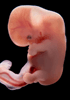

Human Embryo

Carnegie Stage 18 (44 post-ovulatory days)

Most embryos at stage 18 are approximately 44 postovulatory days old and measure 13-17 mm in length. Distinguishing criteria for this stage include cervical and lumbar flexures, distinct notching in the hand plate, the first appearance of the elbow, eyelid folds may appear in more advanced specimens, and auricular hillocks begin to form distinct parts of the external ear.